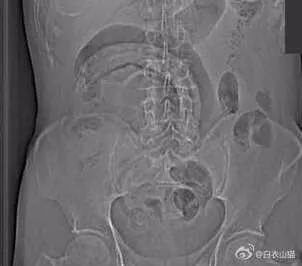

一般情况下,这些肛门异物的病人,来到医院后,医生都会给他上麻醉。把病人麻醉后,在透视下从肛门里夹取直肠里的东西。

一般情况下,用产钳可以取出大部分直肠异物。

如果从肛门里取不出,那就要开膛破肚了。

有时候,病人因为害羞而不肯来医院,耽误了时间后,会造成肠梗阻肠坏死,那肯定要开膛破肚手术啦。